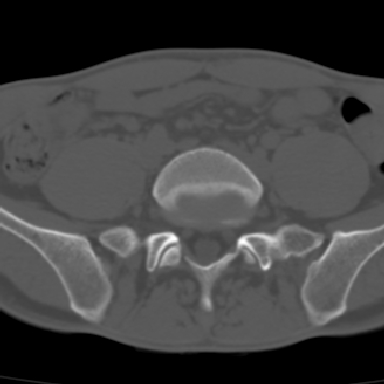

m 30 腰背部不适半年; 清晨时僵硬; 活动症状有所改善

双侧骶髂关节下2/3关节面模糊,毛糙,可见小囊状骨质破坏区.支持强直性脊柱炎.

强直性脊柱炎的早期改变!不仅表现为双侧骶髂关节,第5腰椎与骶椎间的关节突关节也有类似改变。

双侧骶髂关节下2/3关节面模糊,毛糙,髂骨侧可见小囊状骨质破坏区,骶髂关节间隙增宽(软骨破坏期)。支持早期强直性脊柱炎。

双侧骶髂关节下2/3关节面模糊、毛糙,可见小囊状骨质破坏区,呈虫咬状改变,周围可见增生硬化.支持强直性脊柱炎早期表现.

双侧骶髂关节髂骨面硬化,毛糙,小囊变,属于早期强直性脊柱炎